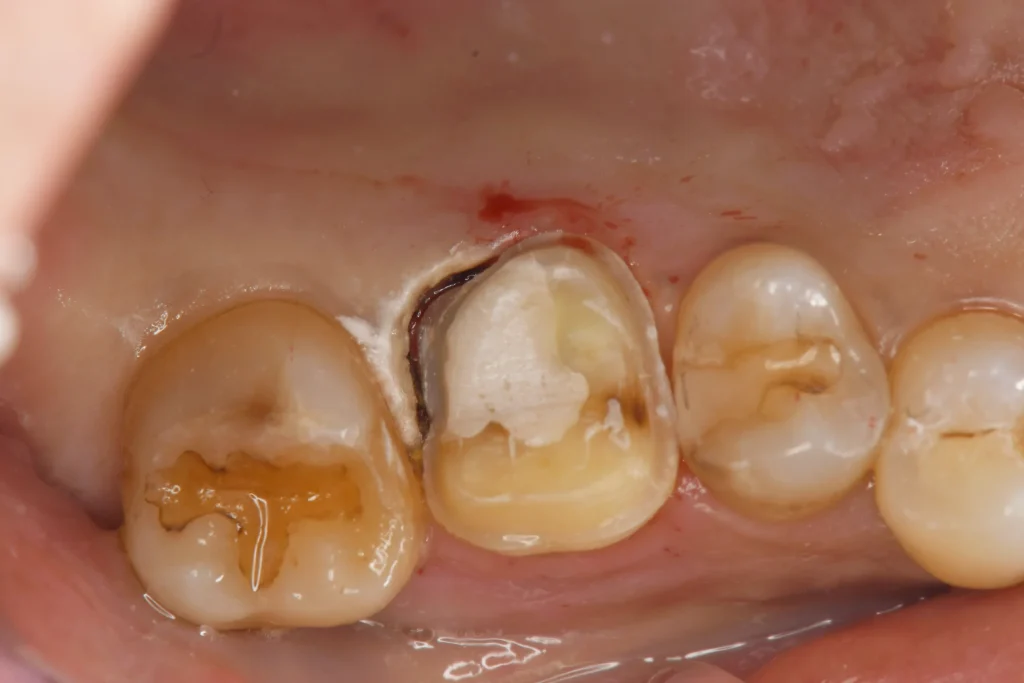

お久しぶりの歯医者さん、歯が欠けたとのことで来院、レントゲン検査にて右上奥歯に神経に達する大きな虫歯が見つかりました。

自発痛なく冷水痛が若干ある程度であったため、歯髄電気診を行なったところ神経が生きていることが確認できました。VPT歯髄温存療法の適応と判断し、ご本人様にその旨をお伝えしたところ、神経を残せる可能性があるなら試したいとのことでこの度VPT治療を行いました。

ラバーダム防湿を行い、丁寧に虫歯の除去を行う。

神経が出る位置まで虫歯が進んでいるため、一旦ここで虫歯除去を停止し壁を作っていきます。

そうすることで、さらに清潔な環境を揃えることができます。

虫歯除去を再開し、すぐに歯髄が露出し出血してきました。

止血と消毒を行い、MTAセメントを貼付していきます。